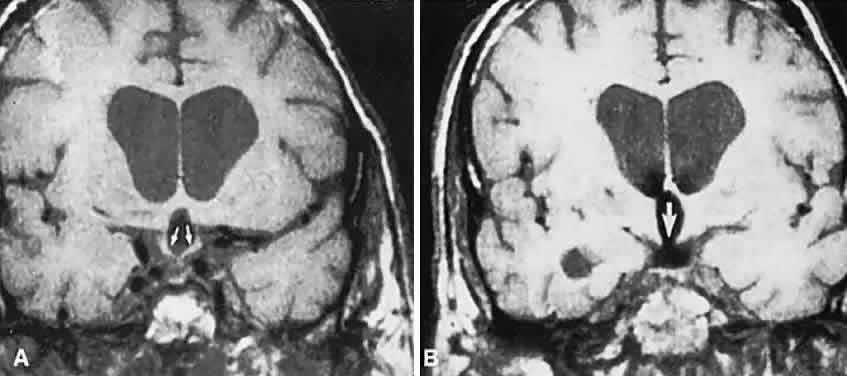

The absence of field defects, for example, in patients undergoing evaluation for amenorrhea, galactorrhea, or sellar enlargement incidentally discovered, does not imply the absence of an adenoma. Obviously, patients with microadenomas, that is, confined within the sella, do not have field defects. From a study24 of 50 cases of pituitary adenomas with chiasmal syndrome, it was concluded that visual disturbance occurs when the chiasm is displaced approximately 10 mm upward (see also Volume 2, Chapter 4, Fig. 6). The modern management of pituitary adenomas should involve several disciplines: current neuroradiologic studies detect microadenomas and provide precise delineation of gross morphology and status of neighboring structures, and mixed MRI signals suggest new or old hemorrhage, cysts, and so forth (Fig. 2); radioimmunoassay techniques assay PRL and other endocrine levels; oral neuropharmacologic agents, such as bromergocryptine, provide a “medical adenomectomy” for hyperprolactinemia and acromegaly; transsphenoidal surgery, including high-illumination microscopical procedures, televised radiofluoroscopic monitoring, and infection control, has all but replaced transcranial approaches; immunohistochemistry techniques have replaced the anachronistic tinctorial designations (e.g., chromophobe, basophilic) with a functional classification.

Fig. 2. Large prolactinoma. Original vision in the right eye (RE) was 8/200, left eye (LE) 1/200, with serum prolactin of 26,000 ng/ml and galactorrhea. Four months of bromocriptine reduced prolactin to 661 ng/ml, vision improved to RE 20/40, LE 20/50. At 3 years, vision was as follows: RE 20/30, LE 20/20; prolactin was 25.9 ng/ml. Enhanced magnetic resonance imaging. Sagittal (A) and coronal (C) images at diagnosis. Sagittal (B) and coronal (D) images at 2-year follow-up, showing dramatic shrinkage of the mass.